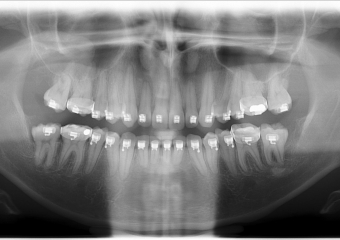

Rx Panorâmico inicial  - Clínica Cliniface

Rx Panorâmico inicial